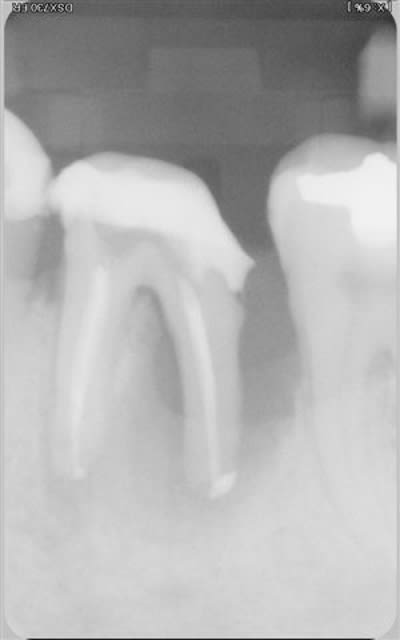

Pour la lésion endo paro sur la 46, j'aurai certainement extrait d'emblée.

Comme tu as fait un super boulot en endo, autant faire le max en paro maintenant. Il conviendrait de saquer la 48 mésioversée et lors de cette chir décoller un peu en antérieur, surfacer la racine distale et la zone inter radiculaire de la 46. Pas de matériau de comblement car il n'y a plus de paroi osseuse pour le soutenir.

Je reste tout de même pessimiste pour cette dent étant donné qu'il semble y avoir du tartre sur toute la hauteur de la racine distale. Quelle est la possibilité de réattache dans ce cas??? noah?

Je pense qu'il est bon de rappeler que tous nos actes endodontiques et parodontaux (pour ne citer qu'eux) sont basées sur des principes biologiques, qu'il est impossible de contourner.

La cicatrisation parodontale a largement été décrite et repose sur plusieurs impératifs cellulaires : présence de paroies osseuses, présence d'un ligt parodontal intact. Est ce des éléments présents dans le cas présenté .... non.

Tu peux toujours combler avec de la poudre de perlinpimpin, mais dépêches toi de faire une radio juste à la fin de ta chir, c'est le seul moment où tu auras le sentiment d'avoir régénéré de l'os !!

Il est tout aussi important de parler de pronostic que de parler de diagnostic. Et il y a des fois où l'extraction est la seule issue...